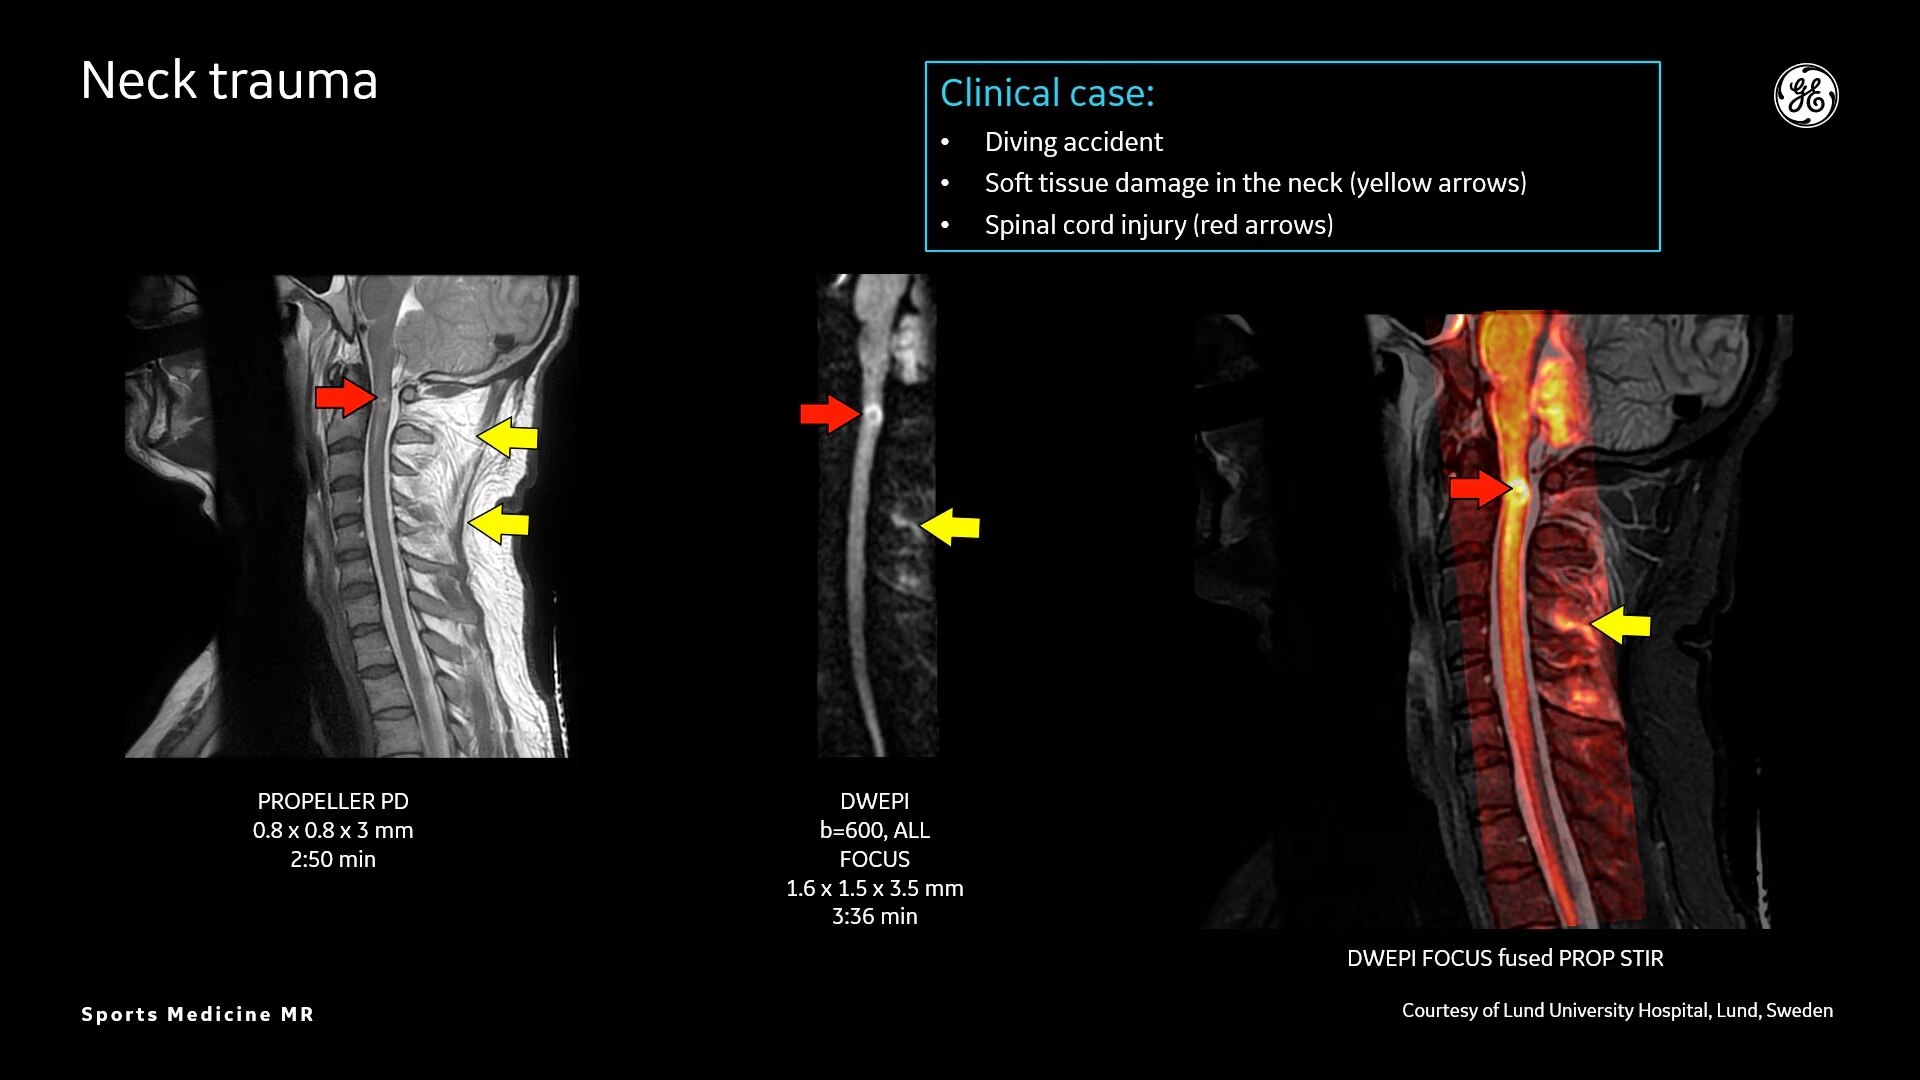

Sports Medicine Imaging

MR technology can scan both soft-tissue and bone injuries, all perfectly co-registered

AIR™ Recon DL provides high-resolution images with increased SNR at markedly reduced scan times. This technology optimizes the depiction of even small injuries, such as meniscal, labral and ligament tears. The reduction in scan times increases flexibility for individually tailored MR protocols with an additional oZTEo sequence for detailed fracture assessment.